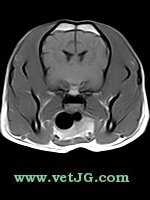

RESONANCIA MAGNÉTICA

TC

AXIAL